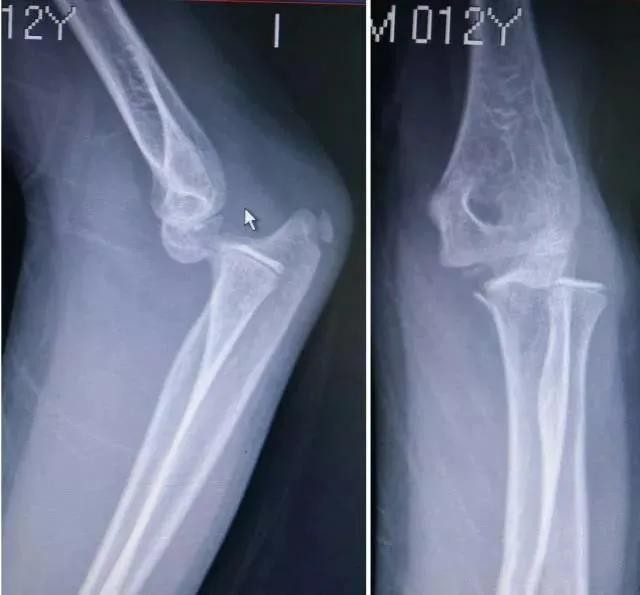

四、肘关节脱位X线图

肘关节脱位分前方脱位、侧方脱位和后方脱位。